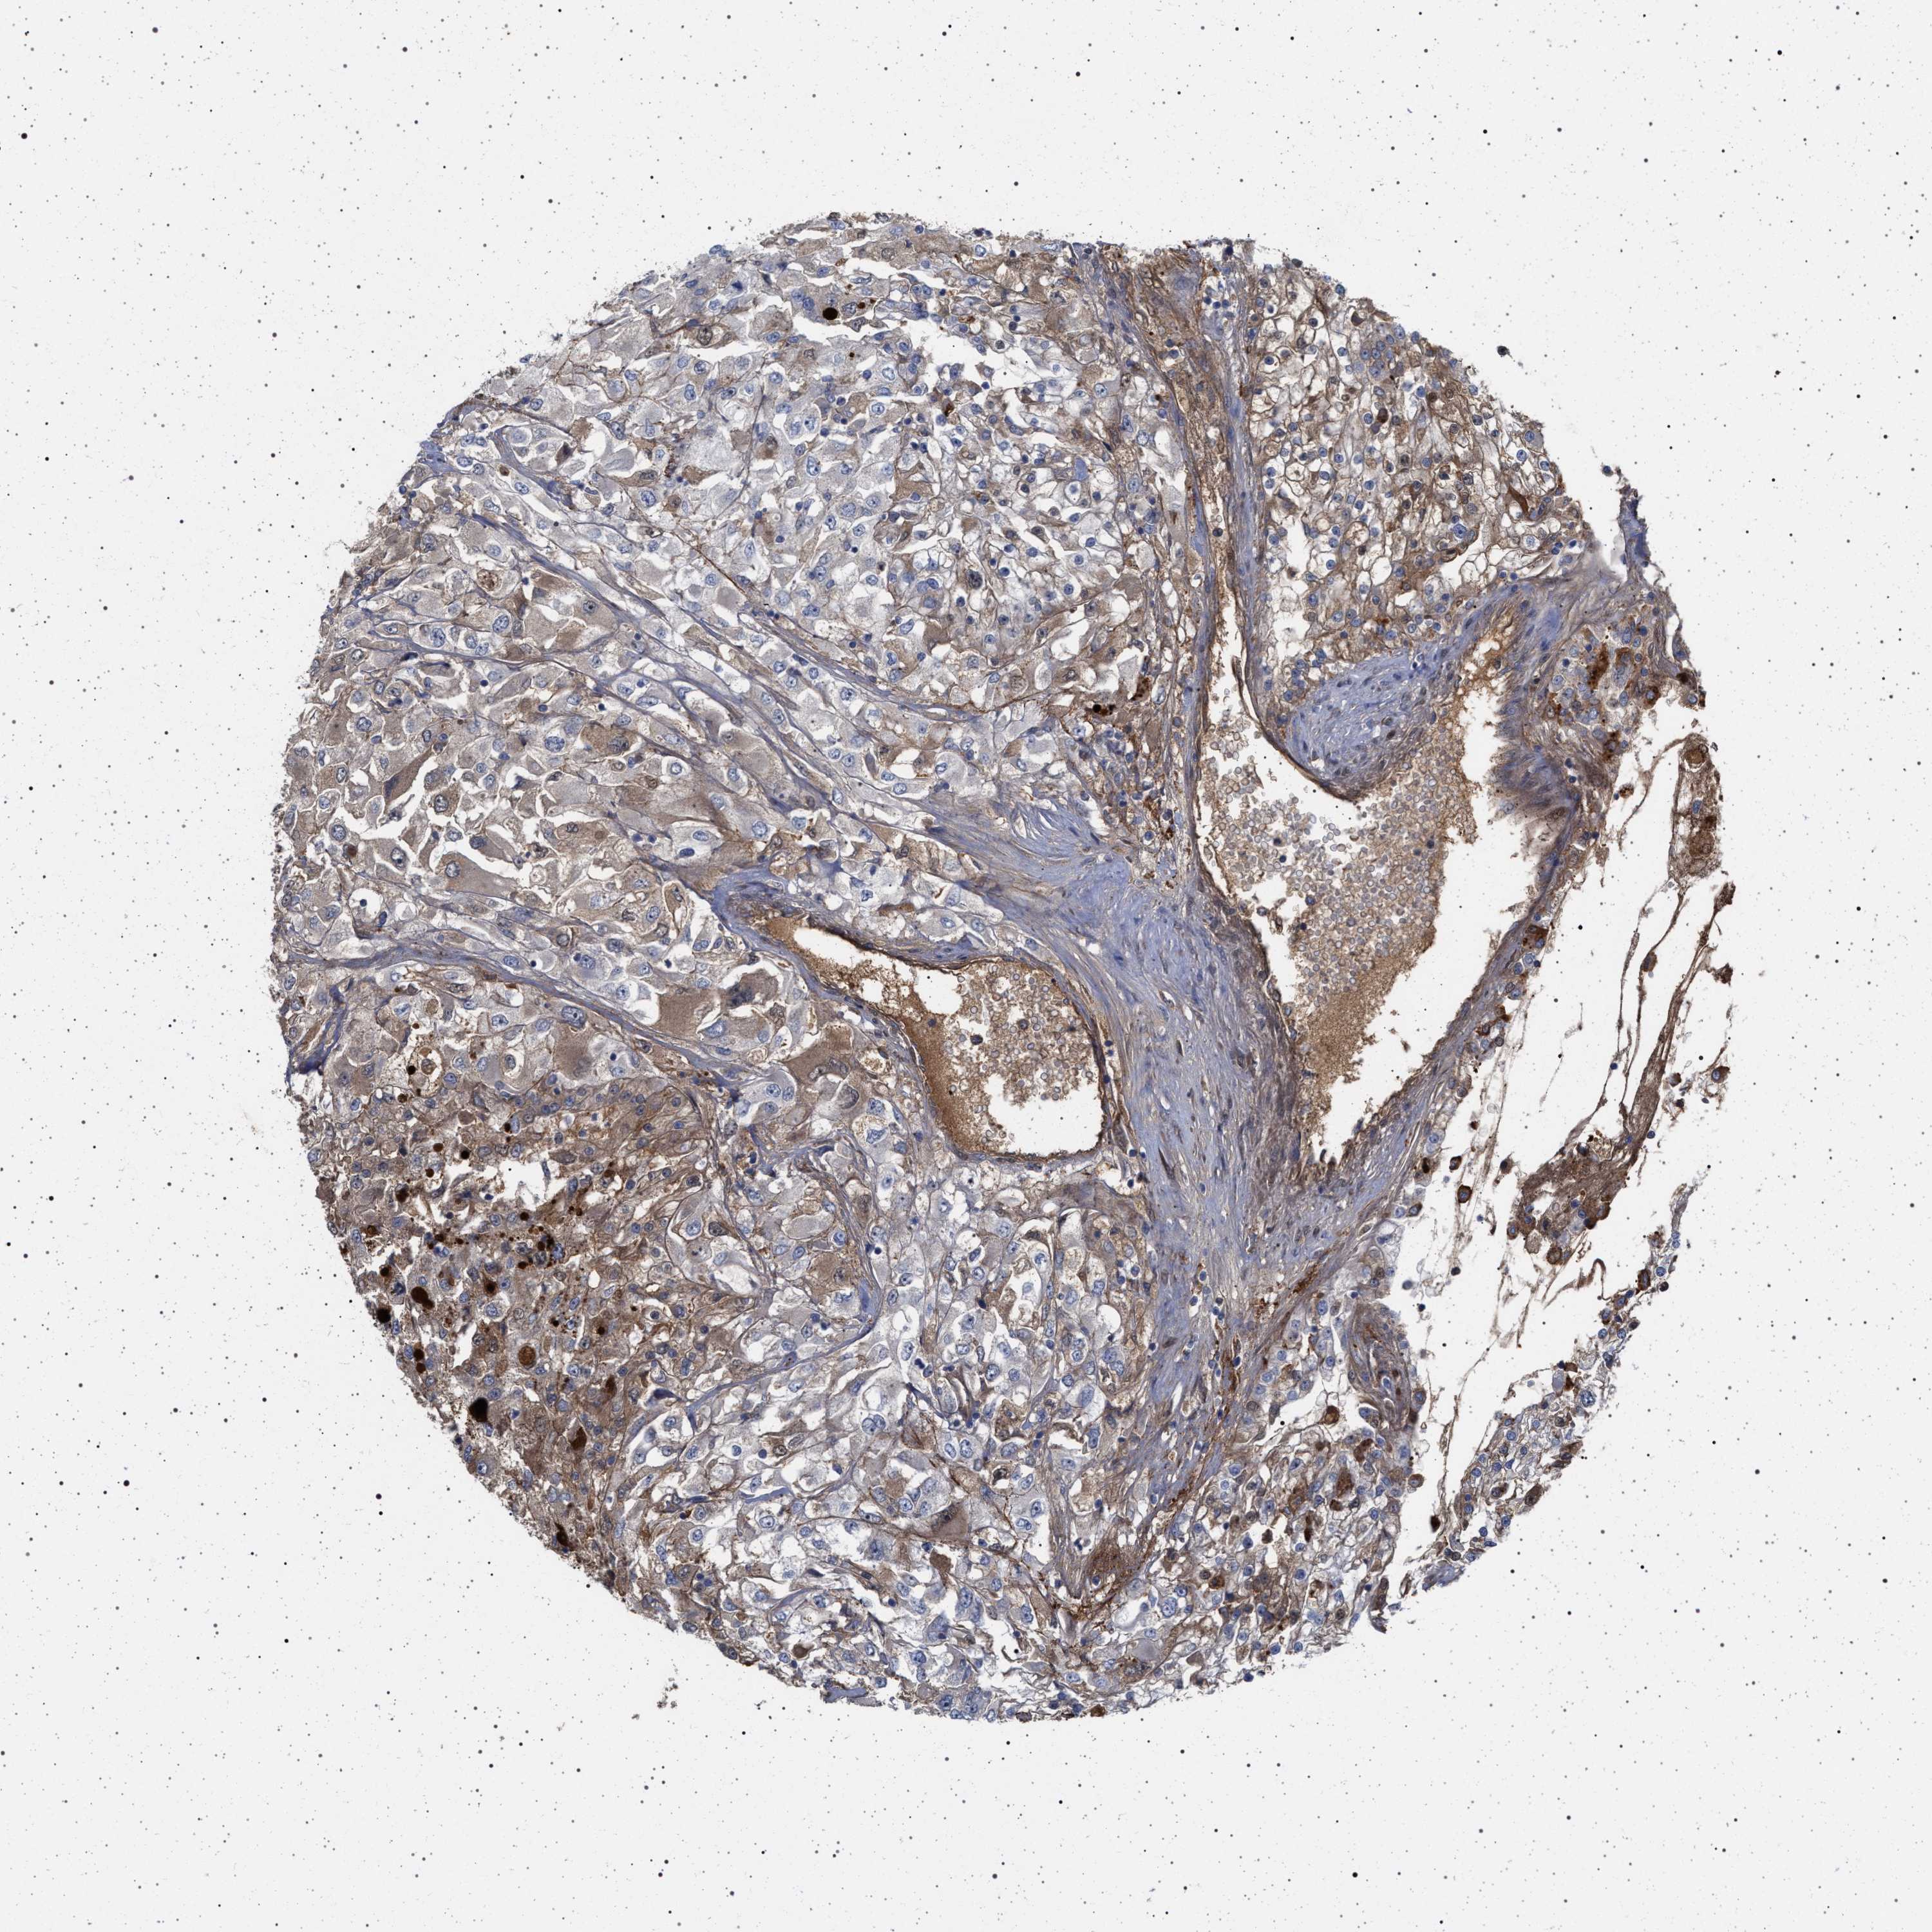

KIDNEY RENAL CLEAR CELL CARCINOMA (VALIDATION) - Interactive survival scatter ploti

The Survival Scatter plot shows the clinical status (i.e. dead or alive) for all individuals in the patient cohort, based on the same data that underlies the corresponding Kaplan-Meier plots. Patients that are alive at last time for follow-up are shown in blue and patients who have died during the study are shown in red.

The x-axis shows the expression levels (FPKM) of the investigated gene in the tumor tissue at the time of diagnosis. The y-axis shows the follow-up time after diagnosis (years). Both axes are complimented with kernel density curves demonstrating the data density over the axes. The top density plot shows the expression levels (FPKM) distribution among dead (red) and alive patients (blue). The right density plot shows the data density of the survived years of dead patients with high and low expression levels respectively, stratified using the cutoff indicated by the vertical dashed line through the Survival Scatter plot. This cutoff is automatically defined based on the FPKM cutoff that minimizes the p-score. The cutoff can be changed by dragging the vertical line or by entering a cutoff value in the square labeled "Current cut-off".

Under the Survival Scatter plot the p-score landscape (black curve; left axis) is shown together with dead median separation (red curve; right axis). Dead median separation is the difference in median mRNA expression between patients who have died with high and low expression, respectively. It is calculated as follows: median FPKM expression of dead patients with high expression - median FPKM expression of dead patients with low expression. This is intended to aid the user in visually exploring custom cutoffs and the associated p-scores and dead median separation.

Individual patient data is displayed and can be filtered by clicking on one or more of the category buttons on the top of the page. Categories describing expression level and patient information include: high, low, alive, dead, female, male and tumor stages. The scale of the x-axis can be toggled between linear and log-scale by clicking on the "x log" button. Mouse-over function shows TCGA ID, patient information and mRNA expression (FPKM) for each patient.

& Survival analysisi

Kaplan-Meier plots summarize results from analysis of correlation between mRNA expression level and patient survival. Patients were divided based on level of expression into one of the two groups "low" (under cut off) or "high" (over cut off). X-axis shows time for survival (years) and y-axis shows the probability of survival, where 1.0 corresponds to 100 percent.

RBM48 is validated prognostic, high expression is favorable in Kidney Renal Clear Cell Carcinoma (validation)

Best expression cut offi

Based on the FPKM value of each gene, patients were classified into two groups and association between prognosis (survival) and gene expression (FPKM) was examined. The best expression cut-off refers the FPKM value that yields maximal difference with regard to survival between the two groups at the lowest log-rank P-value. Best expression cut-off was selected based on survival analysis .

When clicking on this number, the vertical dashed line indicating cut-off, the interactive survival plot, and the Kaplan-Meier curve will be adjusted to show results based on the best expression cut-off.

: 6.27

TCGA RNA samplesi

RNA-seq data is reported as average FPKM (number Fragments Per Kilobase of exon per Million reads), generated by the The Cancer Genome Atlas (TCGA) .

Normal distribution across the dataset is visualized with box plots, shown as median and 25th and 75th percentiles. Points are displayed as outliers if they are above or below 1.5 times the interquartile range. FPKM values of the individual samples are presented next to the box plot.

Average pTPM 7.4

Number of samples 100